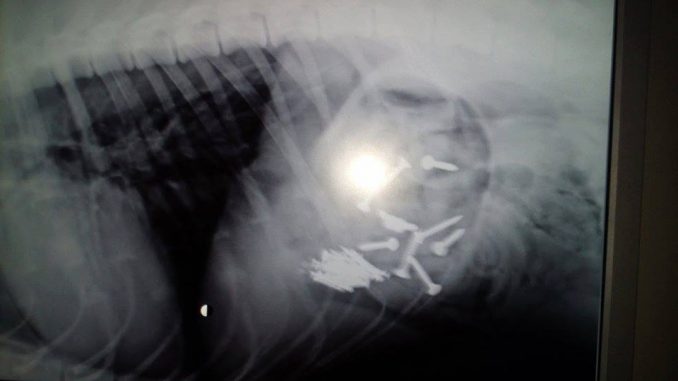

Uzenina se šrouby jako návnada může ublížit i vašemu mazlíčkovi. Městská policie v Košťanech varuje majitele psů, že ve městě bylo zaznamenáno několik pokusů o zranění psů nebezpečnou návnadou, která se skládá z uzeniny se šrouby.

Buďte tedy obezřetní při venčení svých čtyřnohých miláčků a pečlivě zkontrolujte i své zahrady. V případě důvodného podezření nebo zjištění návnady volejte Městskou policii Košťany na tel. 606 743 087 nebo Policii ČR 158.